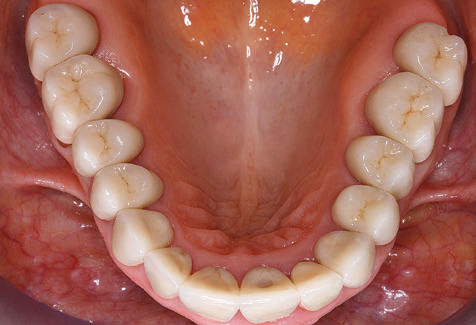

A 52-year-old patient presented in our clinic for the first time in 2004 following tooth loss in the third quadrant, expressing a desire for a new prosthetic restoration. Periodontal and radiological diagnostics revealed the need for extensive periodontological treatment. In addition, teeth 48, 28 and 27 were attributed a very poor prognosis and were subsequently extracted (Fig. 1). Following the successfully completed, systematic periodontological treatment, a fixed dental implant was inserted with the introduction of five implants in tooth regions 35, 36, 37, 46 and 47. Prosthetic treatment of the natural teeth was effected with veneered zirconium dioxide ceramic crowns; the implants were composed of two-piece, individual zirconium dioxide abutments and similarly veneered crowns made of a zirconium dioxide ceramic (Cercon base colored, Dentsply Sirona Lab). Definitive insertion of the prosthetic restoration occurred in 2005.

Due to the presence of periodontal disease, SPT was performed every three months in the first years following the insertion. The patient demonstrated a high degree of motivation and good compliance. The pocket depths recorded annually revealed a stable periodontal situation with a BOP index of below five per cent. On the basis of the stable periodontal situation and good cooperation on the patient’s part, the recall interval was extended to every six months as of the sixth year of the prosthetic function phase. Following the change in the recall interval, the respective annual documentation of the periodontal status continued to reveal a stable periodontal situation with no increase in the pocket depths and a BOP index below five per cent (Fig. 2a and b).

The ten-year check-up revealed no indications of advancing clinical attachment loss or peri-implant bone substance loss (Fig. 3).